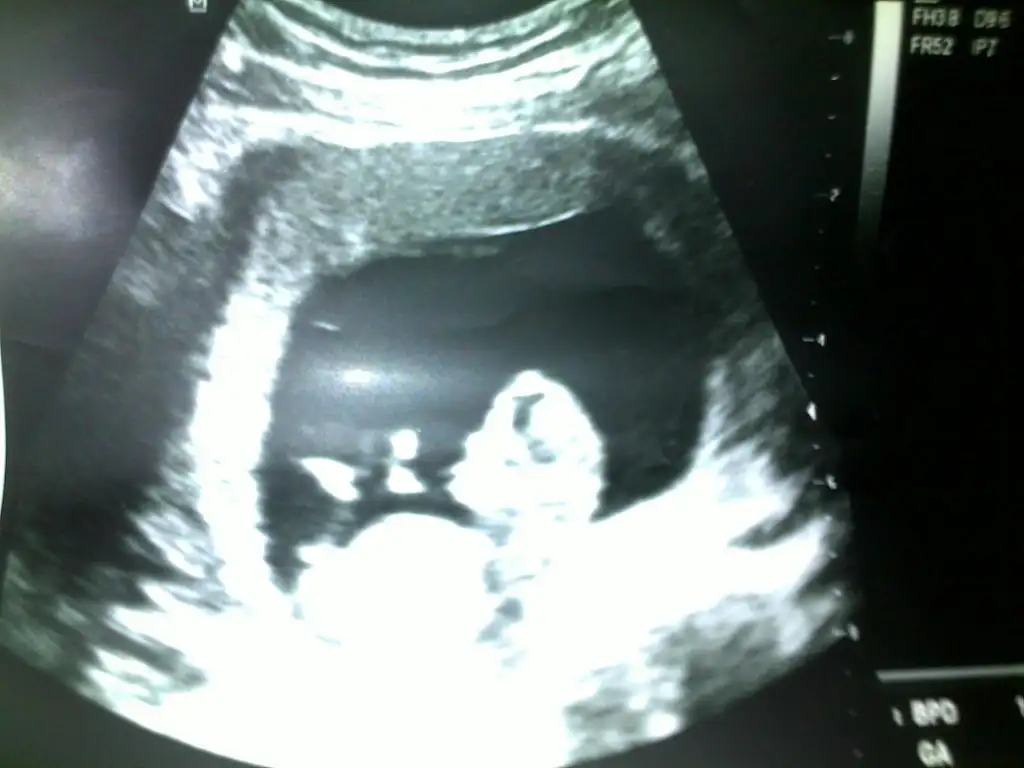

bebişim 11 haftanın içinde.

dünkü doktor ultrasonu. tahmin edebilecek var mıdır.

Rabbim elini ayağını aklını düzgün etsin hayırlı evlat nasip etsin herkese.

Ama gönlümden geçen de ne yalan söyleyeyim kız.